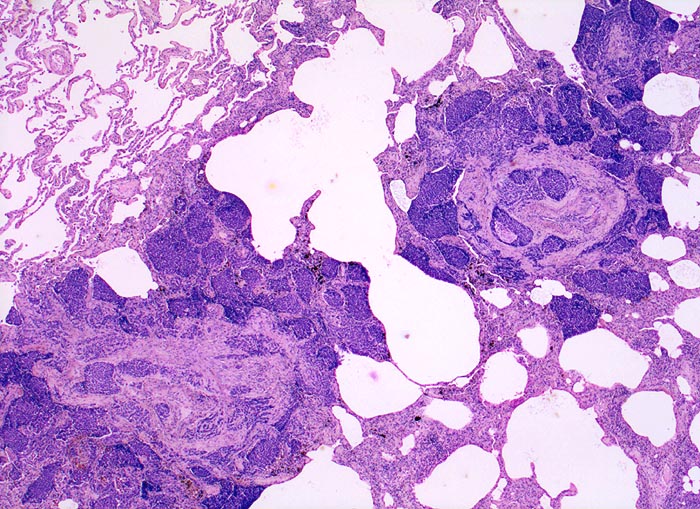

• Sternförmiges Karzinom mit zentraler Vernarbung mit reichlich schwarzem Anthrakosepigment.

• Das Karzinom ist aufgebaut aus tubulären und kribriformen Drüsen.

• In den sternförmigen Ausläufern finden sich erweiterte Endothelausgekleidete Lymphgefässe in der Nachbarschaft von Blutgefässen.

• Die erweiterten Lymphgefässe enthalten solide Tumorzellaggregate.

• Vermehrte Alveolarmakrophagen in den peritumoralen Alveolen mit phagozytiertem Anthrakose- und Hämosiderinpigment (Rauchermakrophagen).

• Peritumorales Lungenemphysem (Traktionsemphysem).